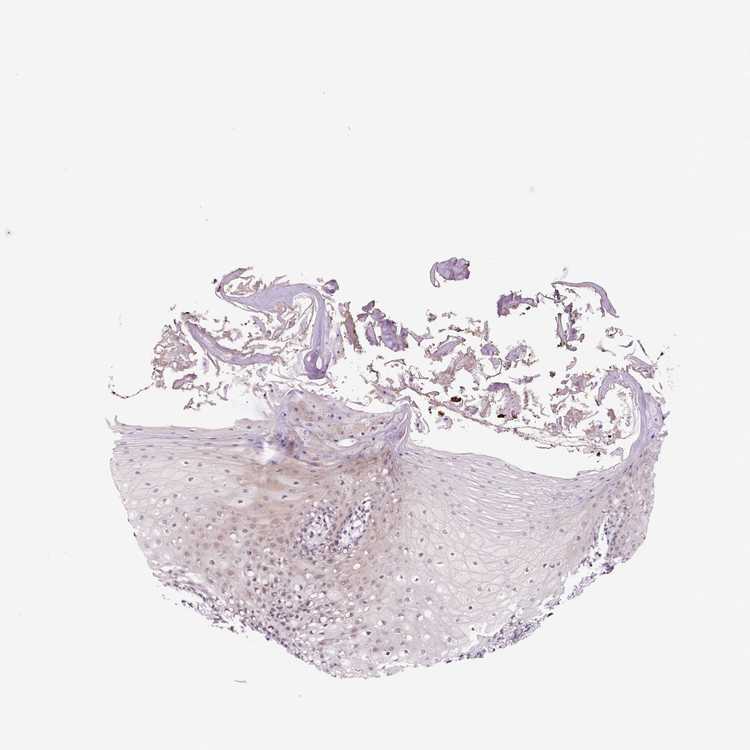

TISSUE PRIMARY DATA ORAL MUCOSA Show tissue menu

ORAL MUCOSA - Antibody stainingi

Antibody staining in the annotated cell types in the current human tissue is reported as not detected, low, medium, or high, based on conventional immunohistochemistry profiling in selected tissues. This score is based on the combination of the staining intensity and fraction of stained cells.

Each image is clickable and will lead to virtual microscopy that enables deeper exploration of all samples and also displays staining intensity scores, fraction scores and subcellular localization as well as patient and tissue information for each sample.

Antibody HPA065958

Squamous epithelial cells Low